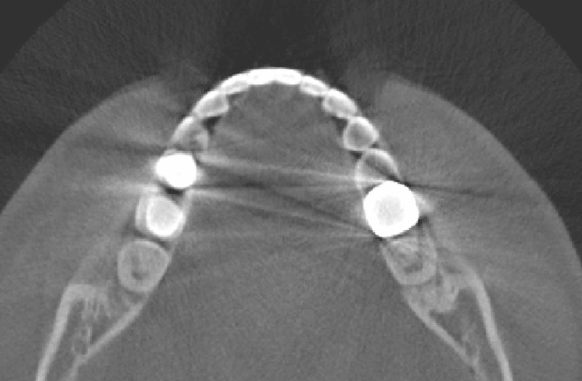

Corollary 1 implies that the streaking artifacts due to Compton scattering can occur between bones and metals, even when (See Fig. 5 (b).)

One of other potential sources of metal artifacts is photon starvation, which occurs when insufficient (possibly zero) photons reach the detector as the X-ray beam passes through a metallic object. This photon starvation generates a similar effect to the noise effect in the metal region Barrett2004 , and the noise contribution is greater from projections that pass through metallic objects than from those that do not. Consequently, these noise effects lead to serious streaking artifacts in the reconstructed image at the points where the beam passes through metallic objects. Numerical and experimental results of streaking artifacts due to photon starvation are well depicted in works by Barrett2004 ; Mori2013 ; vZabic2013 . Streaking artifacts due to photon starvation are verified to be prominent along lines passing through multiple or strong objects with high attenuation coefficients (e.g. metal). Finally, we should mention that streaking artifacts caused by scattering, noise, and photon starvation can be amplified when they are associated with metallic objects Barrett2004 ; DeMan1998 ; Mori2013 ; vZabic2013 (See Fig. 6).

To validate our main results in the clinical CT case, we include CT image of one author’s teeth and mandible in Fig. 6. As shown in this figure, most streaking artifacts occur along the tangent line of boundary of metallic objects. Besides, due to scattering and/or noise effect, the streaking artifacts can occur between the metallic object and the bone, as described in the corollaries of this section.